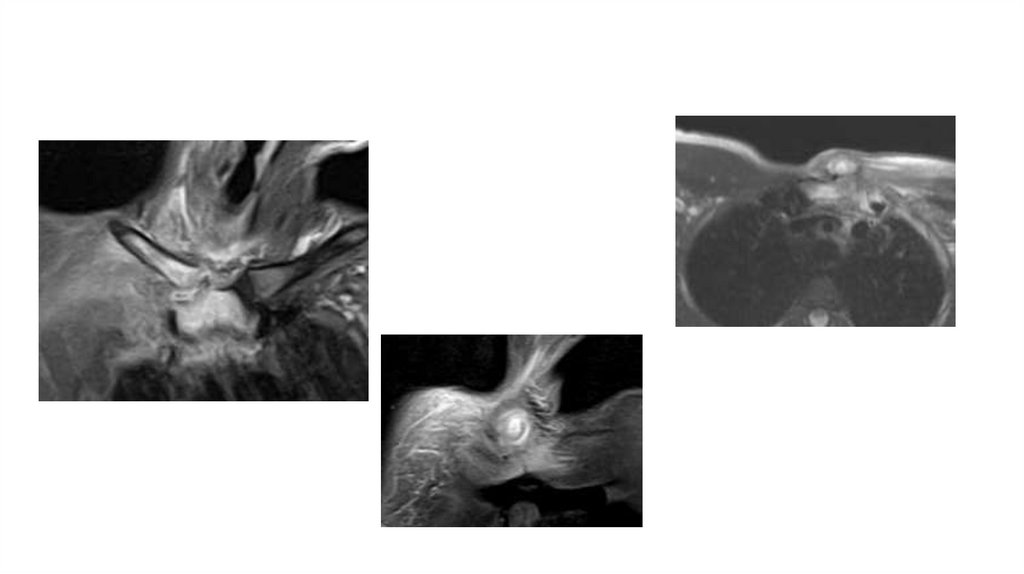

Воспалительные заболевания опорнодвигательного аппарата

заболевания опорнодвигательного аппарата»